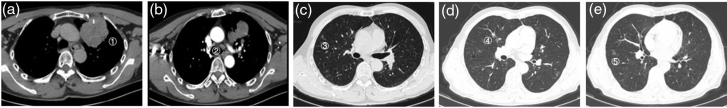

Mesenchymal-epithelial transition factor (MET) exon 14 skipping alterations are rare mutations in non-small-cell lung cancer, associated with high malignancy and poor prognosis. This article presents a case of a patient diagnosed with advanced left upper lung adenocarcinoma characterized by a MET14 skipping mutation. Following first-line treatment with crizotinib, there was a significant reduction in the size of the primary lesion; however, during the course of treatment, an increase in size and prominence of solid components were observed in the right upper lung lesion. A biopsy and subsequent genetic testing revealed an epidermal growth factor receptor L858R mutation in the right upper lung adenocarcinoma, indicating the presence of multiple primary lung cancers. The patient opted against surgical intervention and local treatments, choosing instead a combination therapy regimen that included almonertinib and crizotinib. This treatment approach led to a significant reduction in the size of the right upper lung lesion. The patient's condition has remained stable without any signs of progression, resulting in an overall survival duration exceeding 53 months.